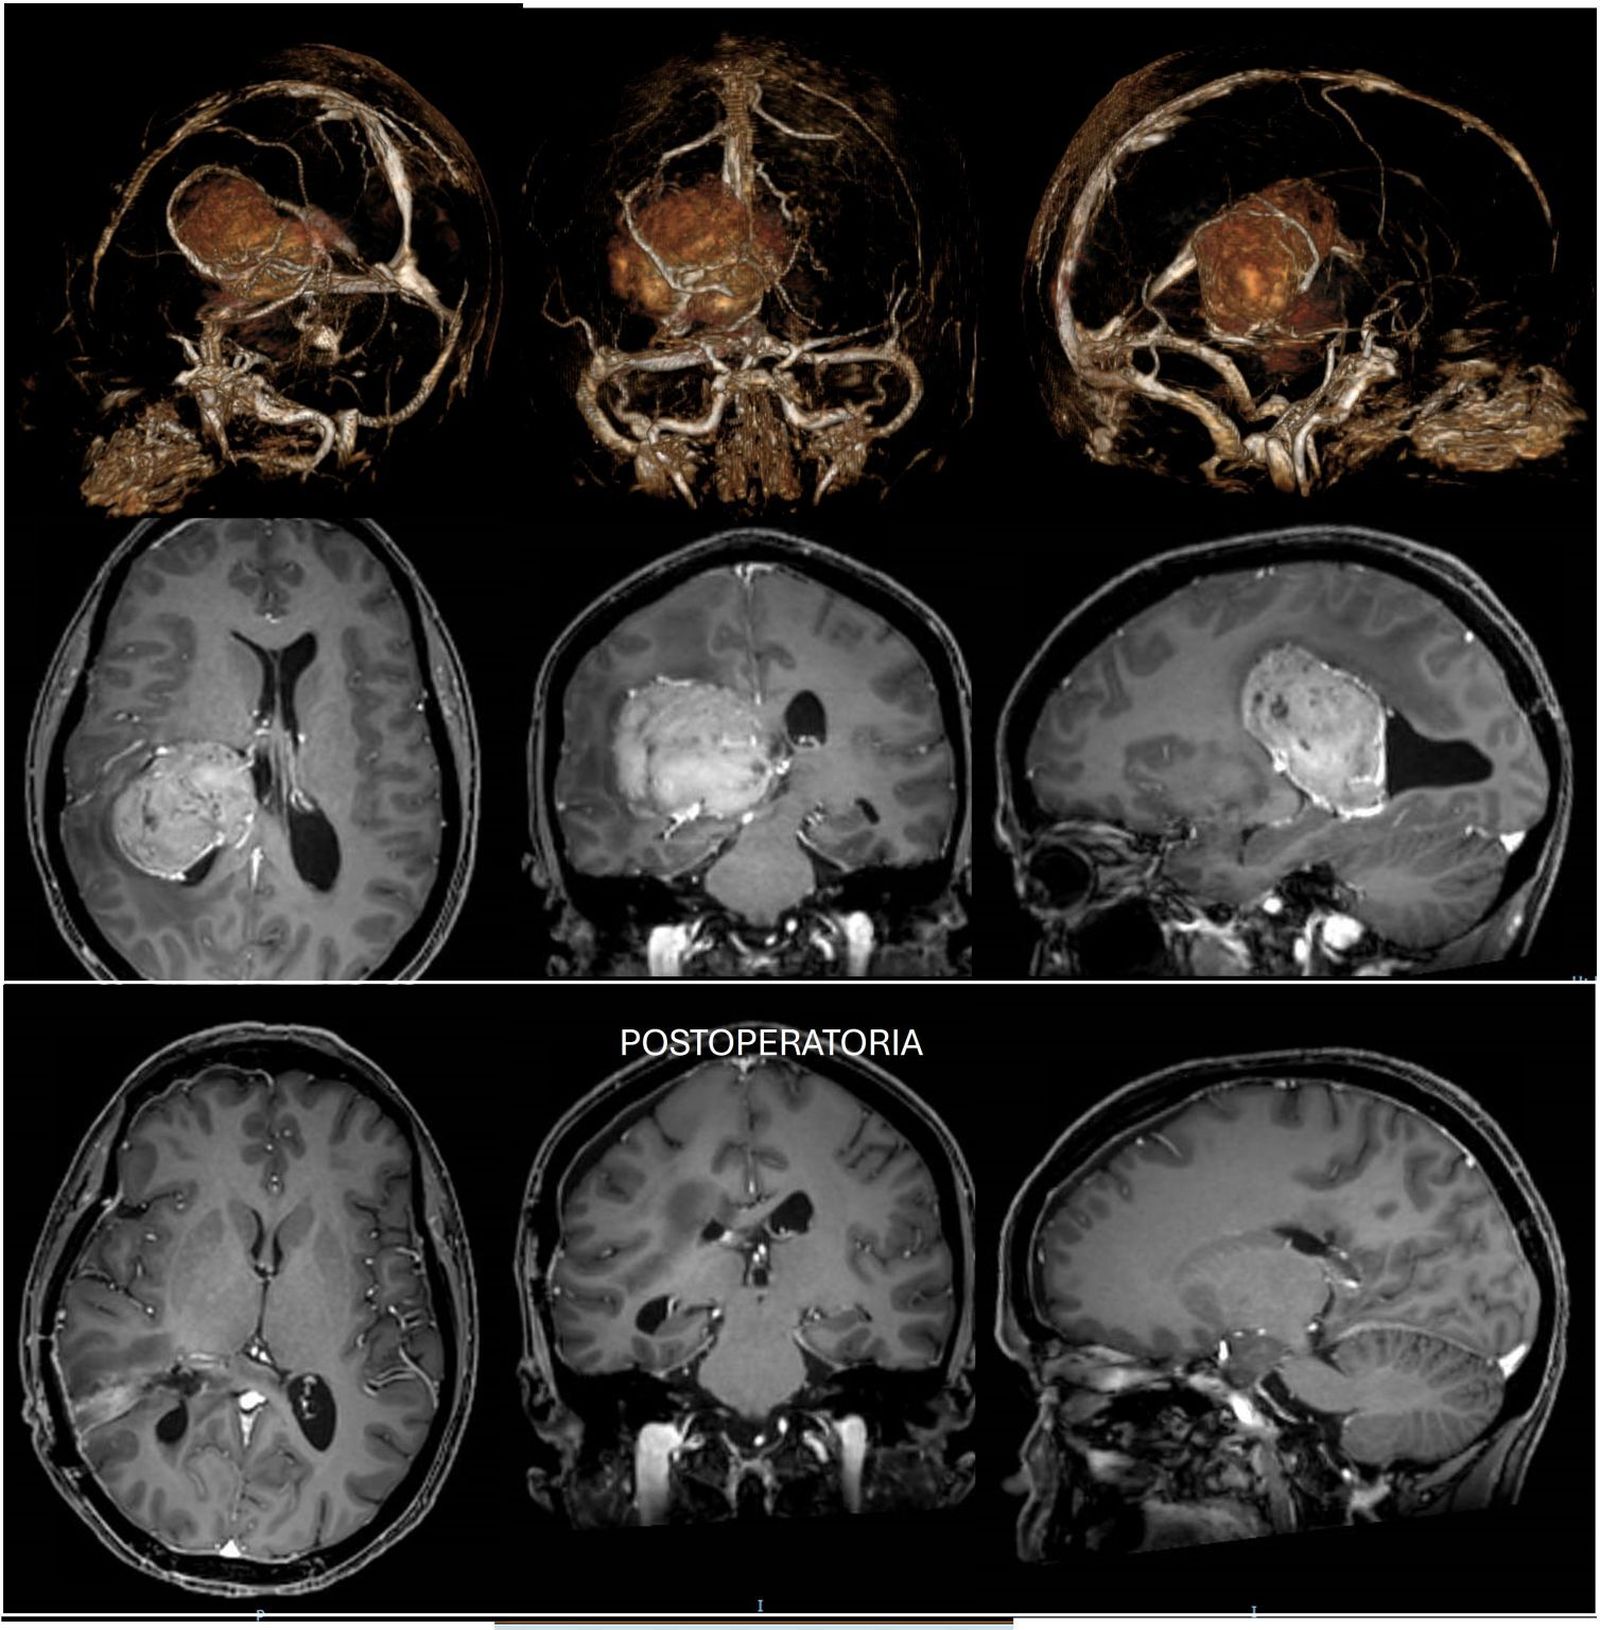

El Hospital Vithas Granada ha llevado a cabo con éxito una complicada intervención quirúrgica para extirpar un tumor en el cerebro de grandes dimensiones, en concreto seis centímetros de diámetro, según ha explicado el centro médico en un comunicado remitido a los medios.

Tras nueve horas de operación, la intervención, que fue llevada a cabo garantizando en todo momento la seguridad y el bienestar del paciente, resultó exitosa gracias al personal médico y las instalaciones del centro y requirió de la utilización de avanzados recursos técnicos como la navegación, el microscopio y la aspiración ultrasónica. Este tumor, caracterizado por síntomas como visión doble e inestabilidad, ha sido intervenido por un equipo de profesionales liderados por el neurocirujano Ángel Horcajadas, coordinador del equipo Neurosalus21.